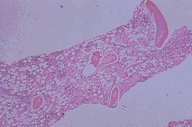

This very low power of a bone marrow biopsy

stained with H&E shows a specimen which is

moderately hypocellular compared to the normal

specimens above.